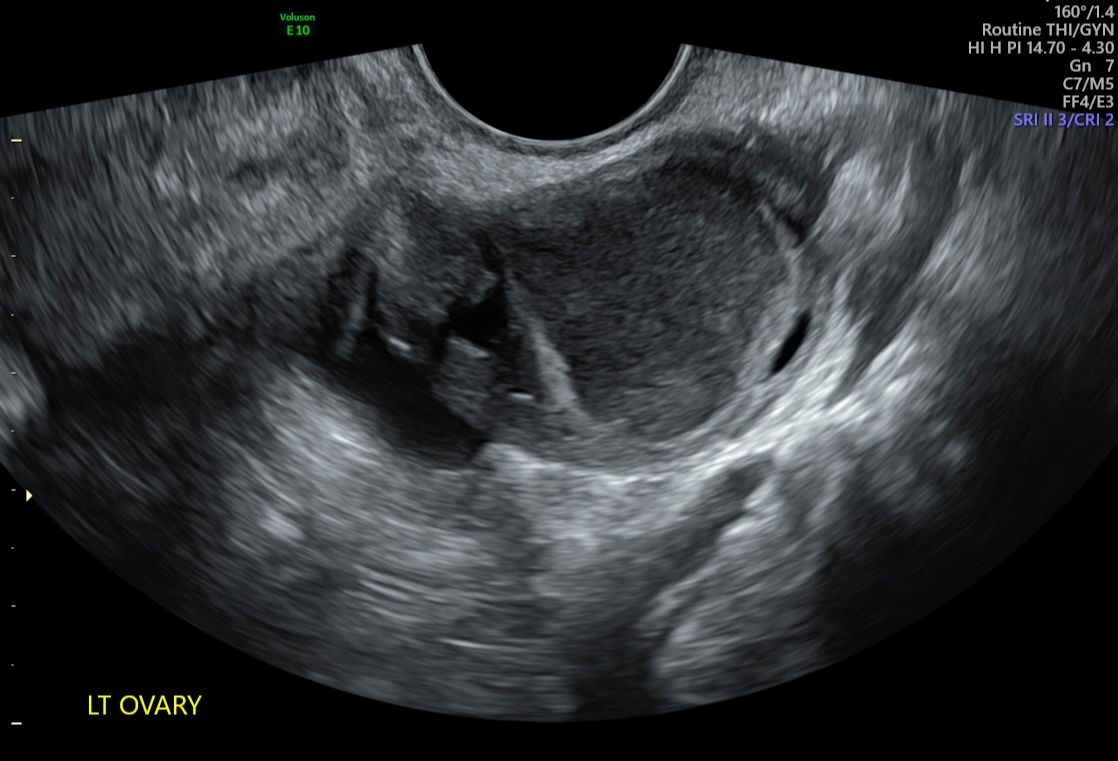

Ovary Endometriosis

Endometriosis affects 1 in 9 women and people assigned female at birth, yet it remains notoriously underdiagnosed. High-quality ultrasound is a crucial first step toward improving recognition and timely diagnosis. This module introduces the core principles of ultrasound for endometriosis, bringing clarity to a complex condition and equipping you with practical skills for everyday clinical application.

• Assessment of the uterus and ovaries using IDEA and MUSA standards.

• Identification of red flags and soft markers for endometriosis.

• Techniques for assessing ovarian mobility and site-specific tenderness.